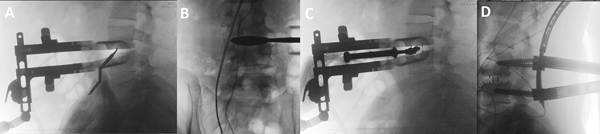

Figura 3: Imágenes de escopia intraoperatoria. (3A) Se marca con disector el medio del disco vertebral. (3B) Tras la discectomía se introducen las pruebas para calcular el tamaño del implante definitivo. (3C) Colocación de la caja intersomática. (3D) Colocación de tornillos pediculares por técnica percutánea habitual.

Fijación vertebral posterior

En todos los pacientes de esta serie se completó la artrodesis intersomática con una fijación posterior con tornillos transpediculares. Tras el cierre de la incisión abdominal colocamos al paciente en decúbito prono y se colocan tornillos por técnica percutánea habitual (Figura 3D).